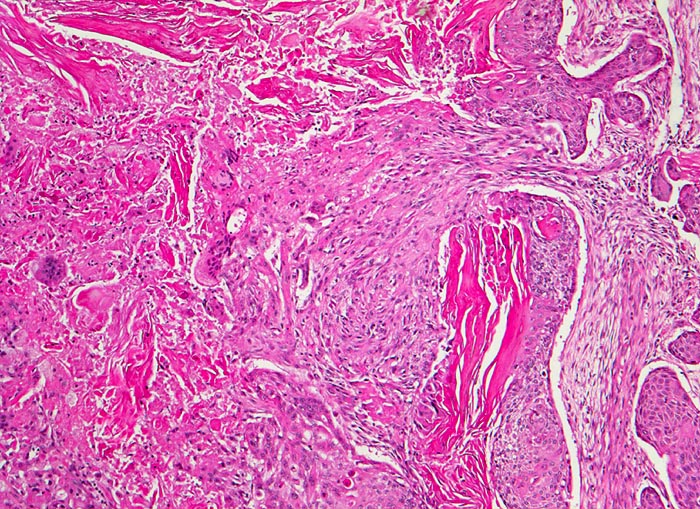

Die häufigeren nicht verhornenden Plattenepithelkarzinome bilden eher Verbände. Die Tumorzellen sind uniformer, das dichte Zytoplasma ist blau-grün gefärbt und scharf begrenzt. Die Zellkerne sind hyperchromatisch und enthalten grosse Nukleolen. Die Abgrenzung des nicht verhornenden Plattenpithelkarzinoms vom Adenokarzinom kann schwierig sein. In der Regel ist das Kernchromatin der Plattenepithelkarzinome dichter und die Nukleolen weniger prominent.

Die Abbildungen zeigen ein verhorntes und ein unverhorntes Plattenepithelkarzinom zum Vergleich.